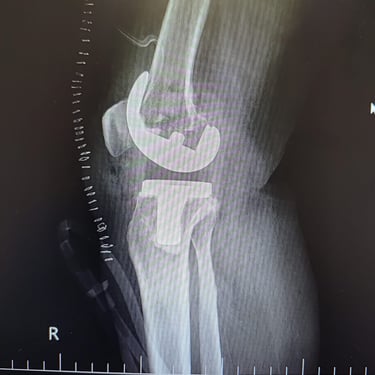

Total knee replacement and partial knee replacement

Gallery